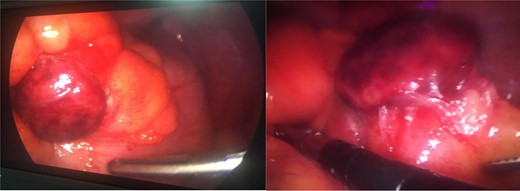

The patient was under the care of Obstetrics/Gynecology and due to persistent pain they elected to take her for emergency laparoscopy exploration. Intraoperative, general surgery team was consulted due to a gangrenous mass adherent to the right lower quadrant abdominal wall, originating from sigmoid colon. The small bowel was inspected from the duodenojejunal junction until the terminal ileum, which was healthy, the colon was inspected until reaching the gangrenous mass, adhesionlysis done and the mass separated from the abdominal wall (Fig. 2). The decision was to proceed for excision of the gangrenous sigmoid appendagitis and deroofing of left ovarian cyst. The postoperative period was uneventful. The histopathology result of specimen reveled necrotic adipose tissue. The ovarian cyst showed a serous cystadenoma.

A laparoscopic view of gangrenous sigmoid appendagitis after adhesiolysis from abdominal wall.